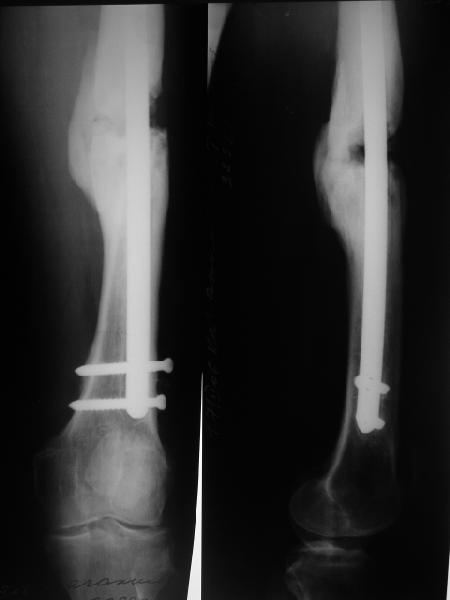

Уважаемые коллеги,В ортопедическое отделение обратился пациент: мужчина 47 лет, который в течение 4-х лет дваждыполучил травму костей, образующих правый коленный сустав. В 2002 v внутрисуставной оскольчатыйперелом проксимального метаэпифиза правой большеберцовой кости; в 2005 v внутрисуставнойоскольчатый перелом дистального метаэпифиза правой бедренной кости. В обоих случаях в разных лечебных учреждениях проводилось оперативное лечение переломов.При осмотре в отделении на основании результатов клинического осмотра и данных визуальныхметодов обследования поставлен диагноз:тугой ложный сустав дистальной трети правой бедренной кости, состояние после накостногоостеосинтеза перелома типа 33-В2.2 ; несросшийся перелом надколенника; неправильно сросшийсяперелом латерального мыщелка правой большеберцовой кости, состояние после металлоостеосинтезаперелома 41-В2.2; сочетанная осевая деформация правой ноги: варусная деформация правого бедра,вальгусная деформация правой голени; посттравматический артроз коленного сустава 4 ст по Kellgren-Lowrence; выраженное нарушение функции ходьбы и опоры. Внешний вид ноги больного, данные рентгенографического обследования и избирательно выделенные компьютерные томограммы приведены в приложении. В именах КТ использовано кодирование уровня по АО, т.е. _41, например, означает проксимальную треть голени.В отделении намечен v очень предварительно v следующий план лечения: 1. Иметь ввиду перспективу тотального эндопротезирования коленного сустава. 2. С учетом п.1 при проведении действий, направленных на устранение ложного сустава бедренной кости не использовать материалы, не подвергающиеся трансформации. 3. В ходе операции, направленной на устранение ложного сустава: А. удалить все металлоконструкции; Б. ревизовать зону пролежня под пластиной на бедре, при наличии признаков достаточной жизнеспособности кости выполнить остеопериостальную декортикацию, дрилинг ложа пластины; В. Удалить рубцовую ткань по плоскости ложного сустава, и в пространстве между костными форагментами, насечь обращенные друг к другу поверхности. Ввести штифт с блокированием (например Stryker с учетом особенностей расположения дистальных блокирующих винтов у этойконструкции). Осуществить остеосинтез с учтанением варусной деформации бедренной кости. Пространство в зоне ложного сустава и пустоты в метафизе бедренной кости заполнить резорбирующимся цементом на основе гидроксиапатита кальция. Для дистальной фиксации использовать винты с переменным шагом резьбы. Вариант:, винты вводить после заполнения метафиза цементом. Дополнительные виды создания межфрагментарной компрессии во встречно-боковом направлении обсуждаются. Г. Быть готовым к кровопотере. Д. Учесть высокий риск инфекции, тромбоэмболических осложнений. Е. Вопрос о внешней иммобилизации решить по результатам оценки стабильности остеосинтеза. Вариант - одноосевой стержневой аппарат для шунтирования гвоздя с модулем на голени и дистракцией коленного сустава в течение 3-5 недель. Просим вашей критики намеченного плана и конструктивных предложений. С уважением к сообществу, Ординатор В.С. Саплин

Чтобы оценить осуществимость такого плана, надо бы увидеть хорошие снимки бедра, лучше в 4 проекциях.

А можно рентгенограммы посмотреть, желательно всей нижней конечности

Несмотря на трафик, нужны ренгенограммы для предоперационного плана, сравнительные снимки всей конечности для определения угла деформации и укорочения конечности, снимок коленного сустава для оценки качества костной массы.